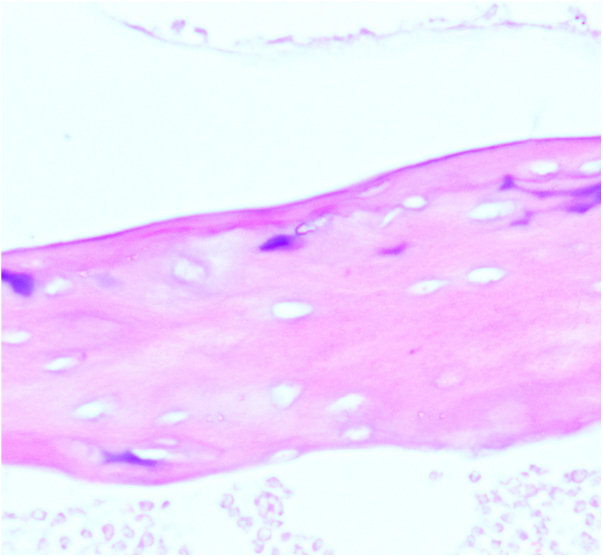

本研究旨在探讨自然杀伤细胞(NK)在股骨头骨坏死(ONFH)中RANKL/RANK/OPG通路中的作用。将C57小鼠分为对照组、观察组(每组10只)和实验组(4只NK细胞敲除小鼠)。采用脂多糖联合甲基强的松龙给药8周,建立激素性股骨头坏死模型。观察组患者皮下注射等量生理盐水。8周后取小鼠外周血,死后取双侧股骨头标本。采用PCR和ELISA技术检测ONFH小鼠外周血和关节液中NK细胞、OPG、RANK、RANKL的表达水平,并与对照组进行比较。与对照组相比,实验组外周血和关节液中NK细胞数量增加。OPG表达下调,RANK和RANKL显著上调,导致成熟破骨细胞数量明显增加。在ONFH患者中,NK细胞上调TNF-α和RANKL,下调IFN-γ和OPG,促进破骨细胞成熟,破坏骨平衡,加速股骨头坏死塌陷,最终加速股骨头坏死的进展。

This study aimed to investigate the role of natural killer (NK) cells in the RANKL/RANK/OPG pathway in osteonecrosis of the femoral head (ONFH). C57 mice were categorized into a control group, an observation group (10 mice each), and an experimental group comprising 4 NK cell knockout mice. A hormone-induced femoral head necrosis model was created by administering lipopolysaccharide combined with methylprednisolone for 8 weeks to the experimental and control groups. The observation group received subcutaneous injections of an equal amount of normal saline. After 8 weeks, peripheral blood was collected from the mice, and bilateral femoral head specimens were obtained post-mortem. Expression levels of NK cells, OPG, RANK, and RANKL in the peripheral blood and joint fluid of ONFH mice were determined using PCR and ELISA techniques, and compared with the control group. The experimental group exhibited an increased number of NK cells in the peripheral blood and joint fluid compared to the control group. OPG expression was downregulated, while RANK and RANKL were significantly upregulated, resulting in a marked increase in the number of mature osteoclasts. In ONFH patients, NK cells were found to upregulate TNF-α and RANKL, downregulate IFN-γ and OPG, promote osteoclast maturation, disrupt bone balance, accelerate femoral head necrosis collapse, and ultimately hasten the progression of femoral head necrosis.